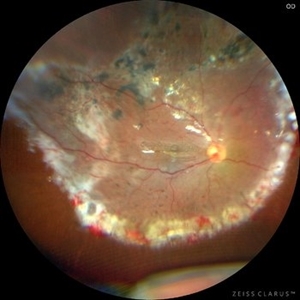

Tapetoretinal Degeneration

Patient 52 years old, Male, progressive loss of vision since the age of 20. Retinography showed mobilization of pigments in osteoblasts, extensive area of atrophy of the pigmentary epithelium and choroid. On fluorescein angiography, typical changes following the characteristic patterns of paracentra retinal retinitis pigmentosa. Autofluorescent fundus with a sectorial autohypofluorescence pattern in the regions of atrophies.

Photographer: JEFFERSON ROCHA DE SOUSA - Retinal Department at Instituto Dr. Suel Abujamra Sao Paulo-Brazil

Imaging device: Clarus 700 - Zeiss, composite of four 135 degree images.

Condition/keywords: pericentral retinitis pigmentosa, tapeoretinal degeneration